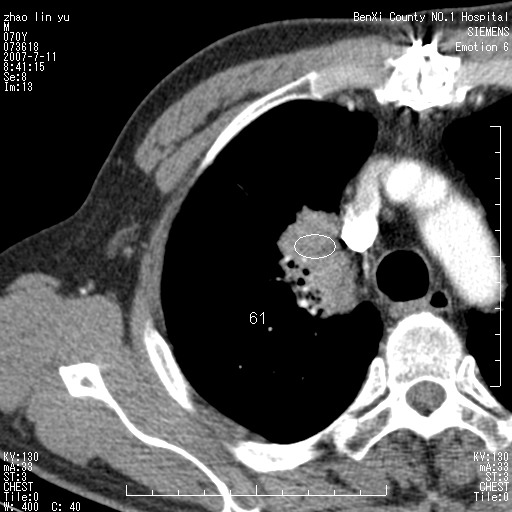

以下是引用王靖旗在2007-7-10 17:12:00的发言:[br] 男、70、咳嗽两个月,半年前换瓣手术,胸片未见异常,于昨天行x片发现右肺上野大片影,行ct扫描,这里是减薄图像,余肺正常。明天晚上会有增强扫描片,到时我会上传。[br][br] 冠状位请大家细看,应该是有意义的,[br][br] 请大家先看平扫发表意见。[br][br]

以下是引用zhangzhongshou在2007-7-10 21:43:00的发言:[br]右肺上叶周围型肺癌,以孤立型细支气管肺泡癌可能性大。